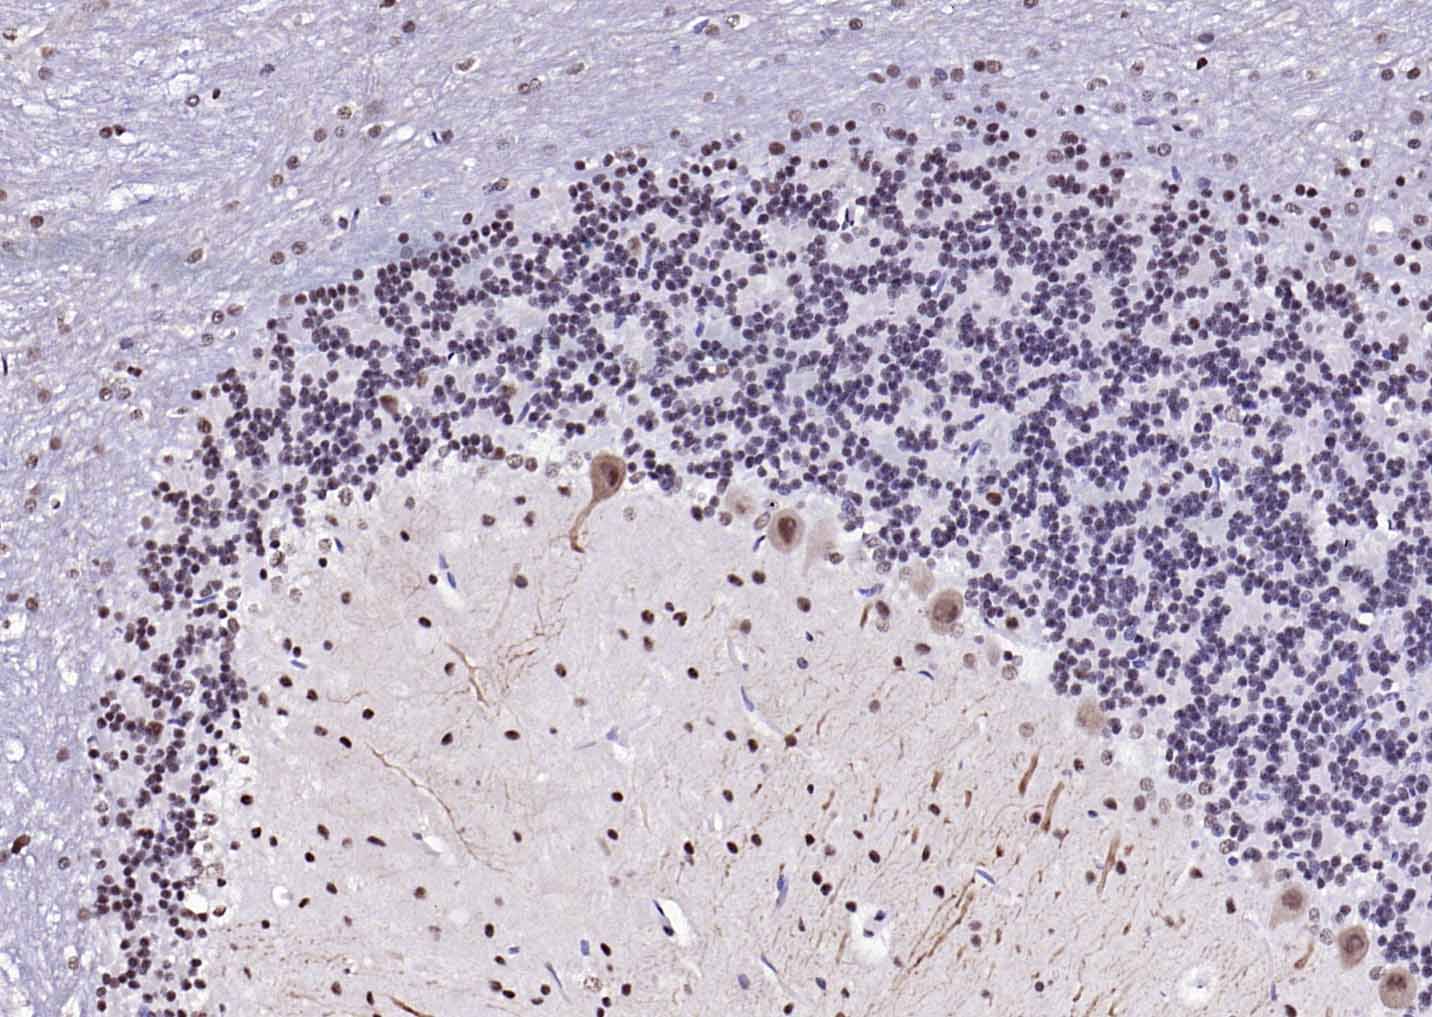

Paraformaldehyde-fixed, paraffin embedded Mouse Cerebellum; Antigen retrieval by boiling in sodium citrate buffer (pH6.0) for 15 min; Antibody incubation with ESR2 Polyclonal Antibody, Unconjugated (bs-0116R) at 1:200 overnight at 4°C, followed by conjugation to the SP Kit (Rabbit, SP-0023) and DAB (C-0010) staining.

Paraformaldehyde-fixed, paraffin embedded Rat Cerebellum; Antigen retrieval by boiling in sodium citrate buffer (pH6.0) for 15 min; Antibody incubation with ESR2 Polyclonal Antibody, Unconjugated (bs-0116R) at 1:200 overnight at 4°C, followed by conjugation to the SP Kit (Rabbit, SP-0023) and DAB (C-0010) staining.